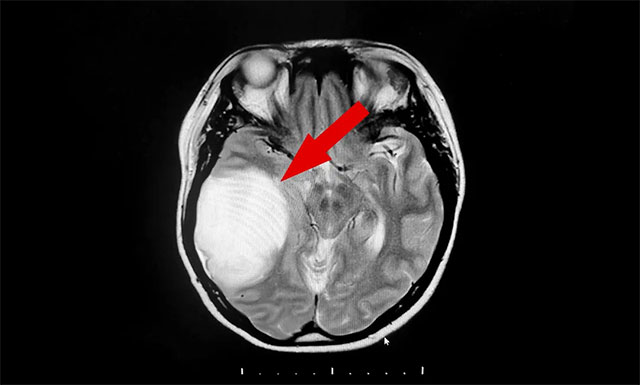

医学前沿 | 四旬女子头痛呕吐竟是颅内巨大胶质瘤 神经外科沈建康教授顺利切除